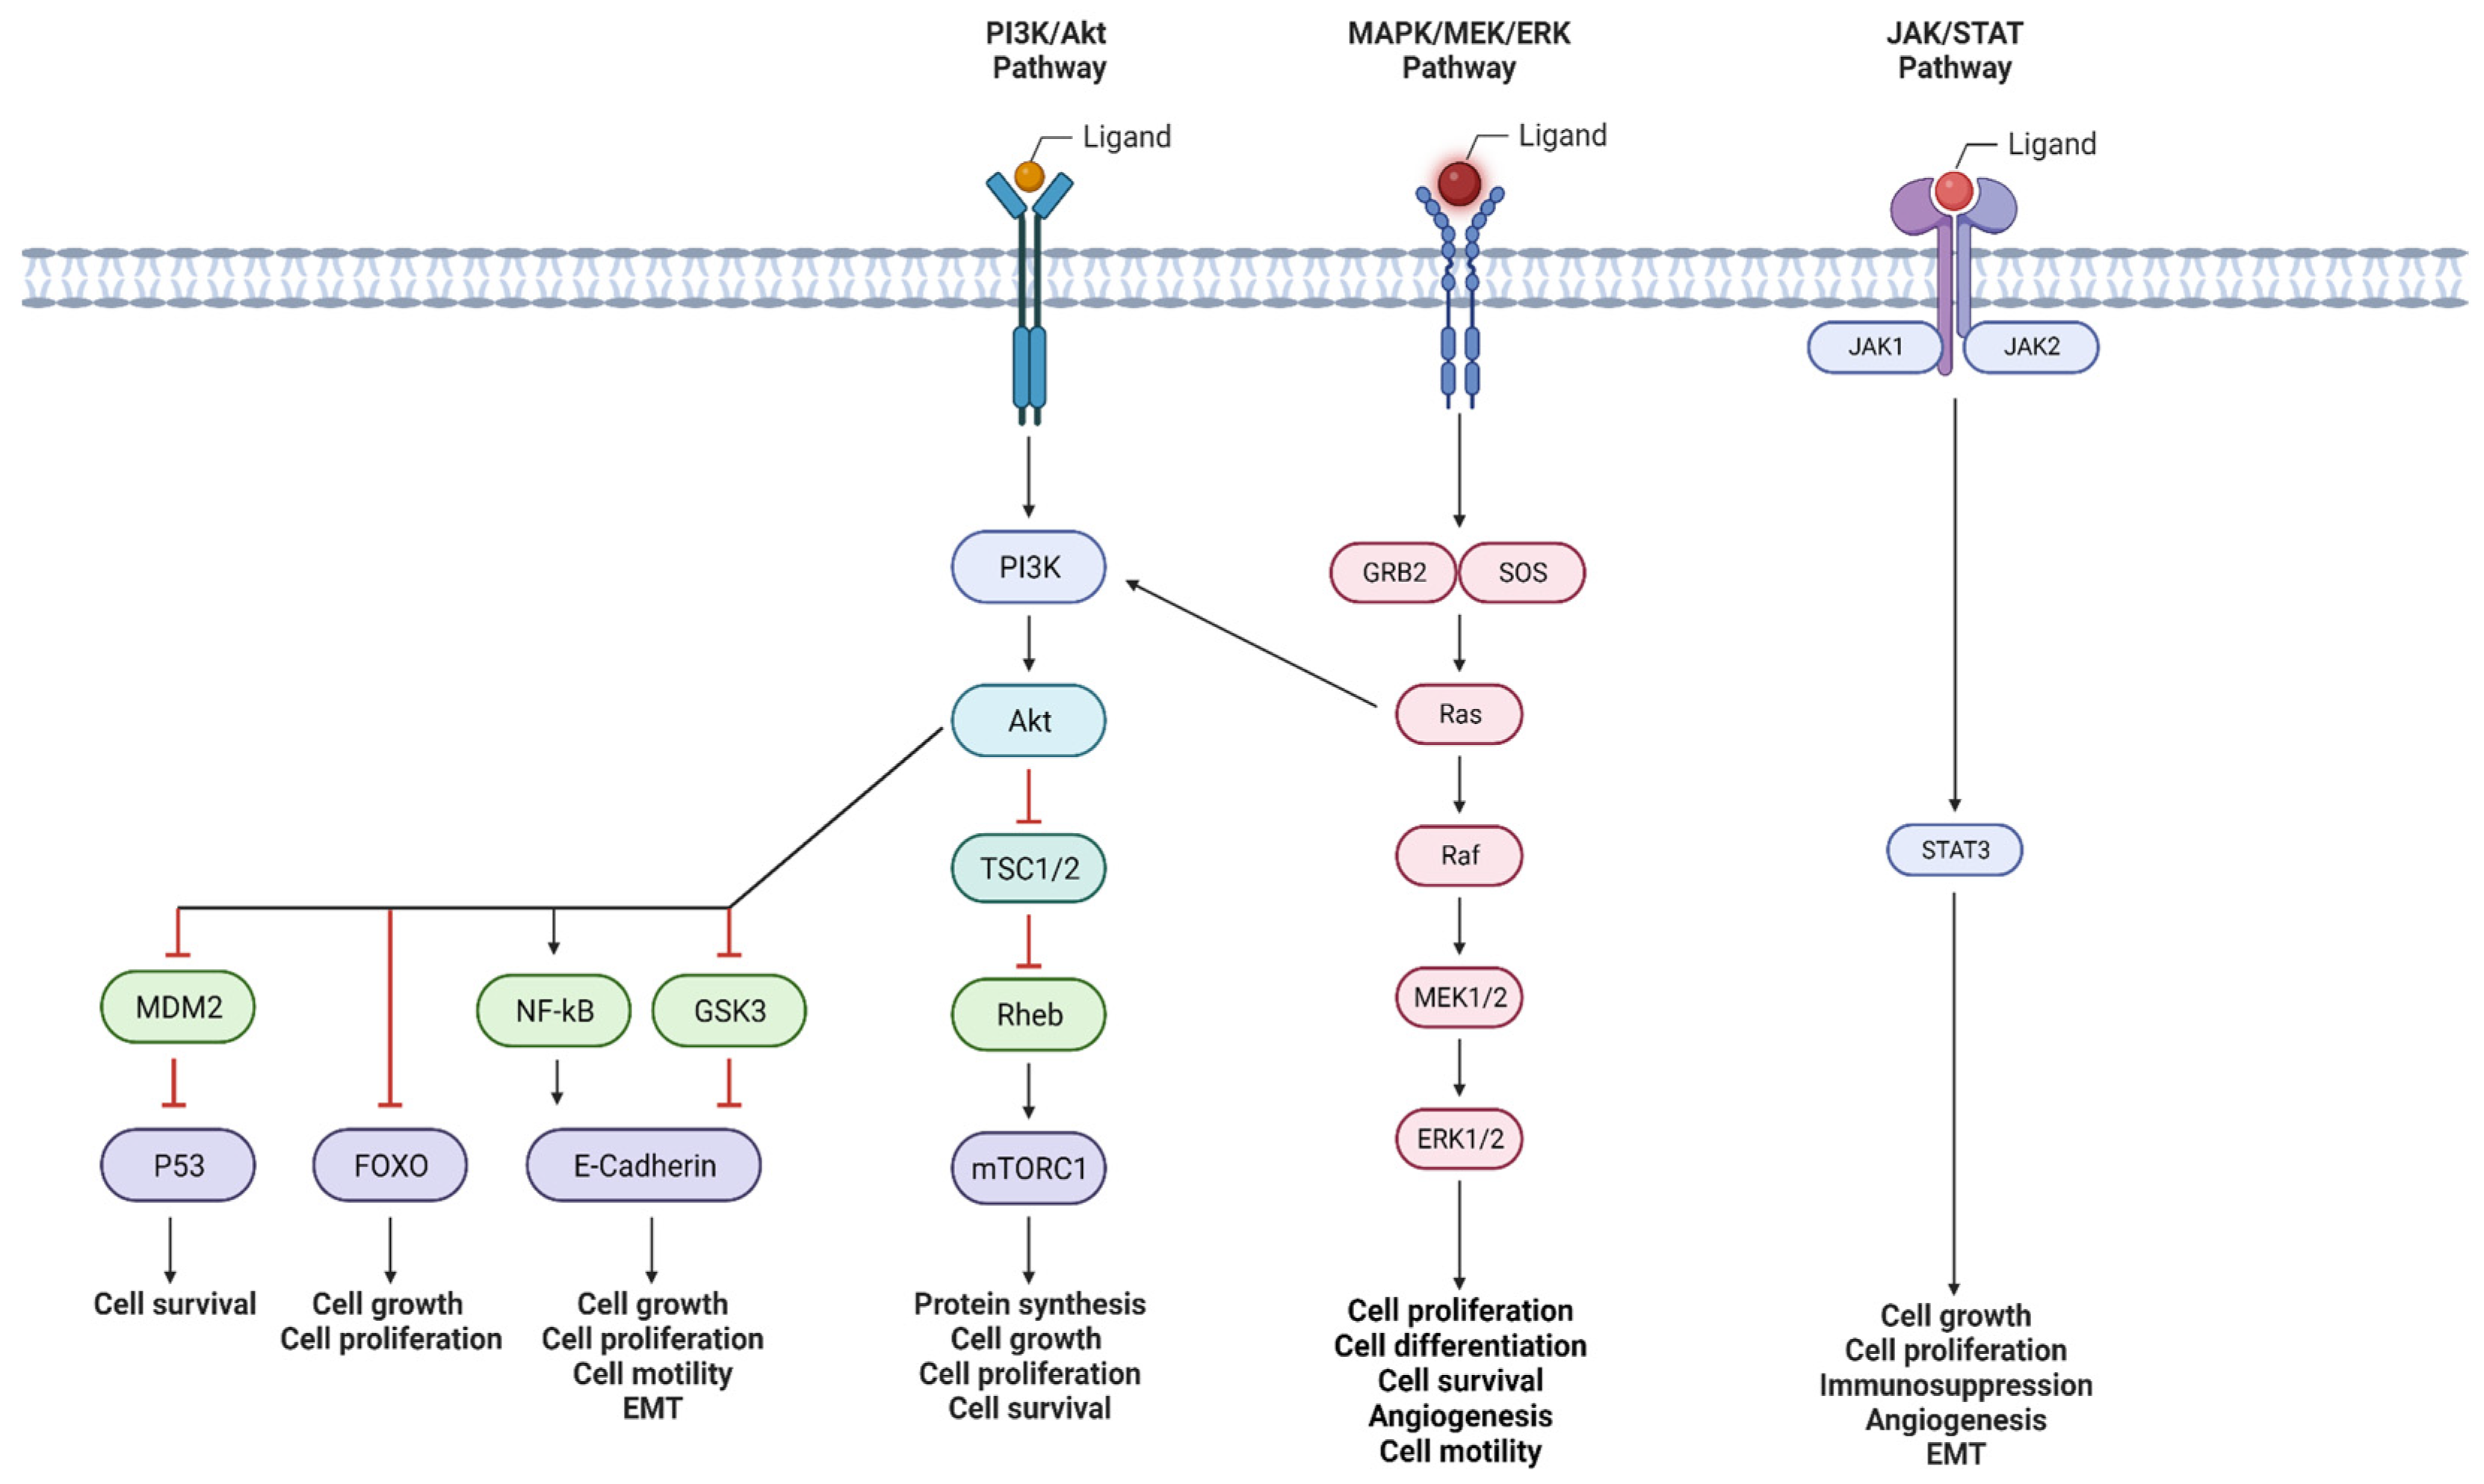

2. Signaling Pathways Involved in Inducing Perineural Invasion

2.1. PI3K/Akt Pathway

2.2. MAPK Pathway

2.3. JAK/STAT Pathway